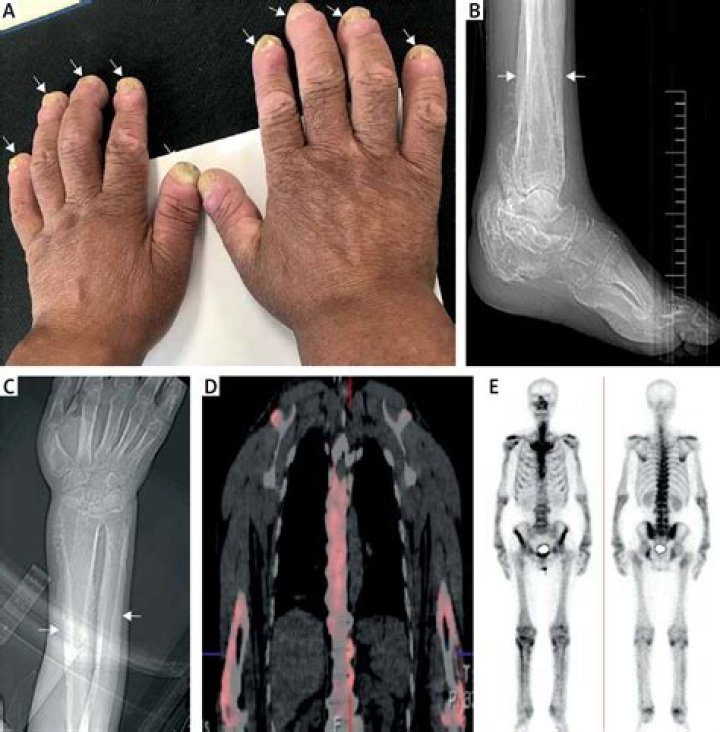

Hypertrophic osteoarthropathy (HOA) is mainly caused by mainly fibrovascular proliferation. It is characterized by a combination of clinical findings, including severe disabling arthralgia and arthritis, digital clubbing, and periostosis of tubular bones with or without synovial effusion.

Hypertrophic osteoarthropathy (HOA) is a medical condition characterized by abnormal proliferation of skin and periosteal tissues involving the extremities and characterized by three clinical features: digital clubbing (also termed Hippocratic fingers), periostosis of tubular bones, and synovial effusions.

Hypertrophic osteoarthropathy is a medical condition combining clubbing and periostitis of the small hand joints, especially the distal interphalangeal joints and the metacarpophalangeal joints. Distal expansion of the long bones as well as painful, swollen joints and synovial villous proliferation are often seen.